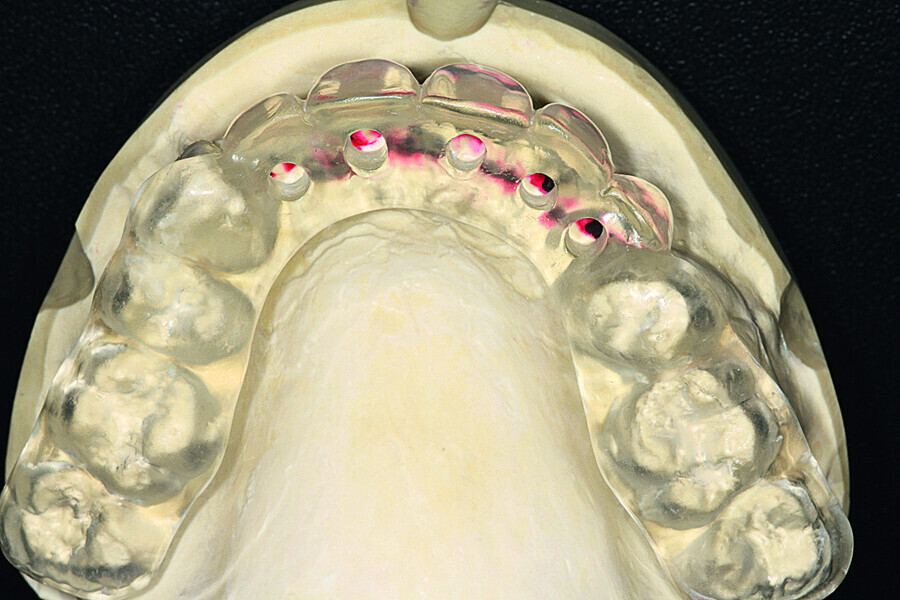

Fig. 12: A key of the added wax was taken and fabricated in clear casting resin.